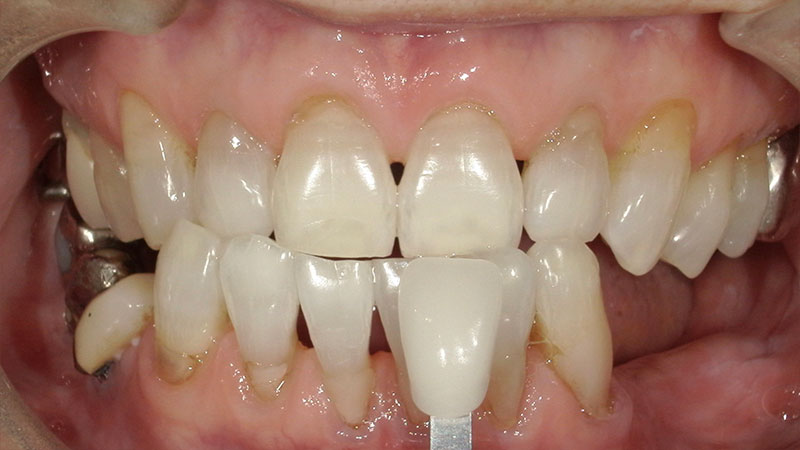

デュアルホワイトニング症例

デュアルホワイトニング症例をご紹介します。

ホワイトニングにはオフィスホワイトニングとホームホワイトニングに分けられます。

オフィスホワイトニングは医療ホワイトニングの一つで歯科医院に来院で施術を受けます。

ホームホワイトニングは専用のマウスピースに薬剤を入れて1日数時間はめるものになります。

デュアルホワイトニングとはオフィスとホームを併用する処置になります。

オフィスのいいところである短時間での漂白と、ホームのいいところである持続的な漂白が可能になります。

今回のように加齢で黄ばんだ頑固な着色も真っ白にできます。

デメリットとして2種類するので手間がかかります。

加齢による歯の黄ばみはクリーニングだけでは綺麗になりません。

また、今回のように歯にまだら模様の変色がある場合はホワイトニングによって目立たなくなります。

今回させていただいたオフィスホワイトニングは1ヶ月集中コースになります。

1ヶ月間通い放題(中2日空ける)の平日のみのお得なコースです。

短期間で一気に白くしたい方、平日に通いやすい方に向いているコースになります。

| 患者様 | 70代女性 |

|---|---|

| 主訴 | 全体的な黄ばみが気になる |

| 治療費 | ベーシックコース77,000円(税込) ホームホワイトニング16,500円(税込) 総額93,500円(税込) |

| 治療期間 | オフィスホワイトニング8回 ホームホワイトニング1ヶ月 |